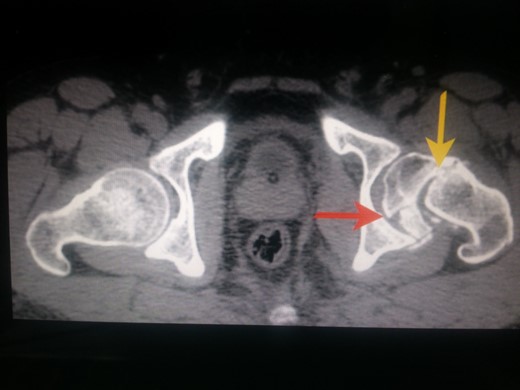

Following trauma patient had left-sided chest pain, frontal headache and severe pain in his left hip region. After hemodynamic stabilization and preliminary treatment for his chest and head injuries, he was evaluated for left hip region pain. Clinically patient had left anterior hip joint line tenderness. Initial X-ray imaging showed impacted subcapital fracture of femur neck, with varus angulation between femur head and neck (Fig. 1), which prompted detailed radiological evaluation. A 3D reconstructed CT scan imaging disclosed a separate fracture line in femur head, with a detached inferior head fragment (Fig. 2); thus, the patient had concurrent ipsilateral fracture of femur head and neck without hip dislocation. We decided to treat this fracture pattern surgically with either osteosynthesis and fixation, or primary total hip arthroplasty. Via posterolateral approach to hip, femur head and neck fractures were exposed. Proximal femur fragment showed severe impaction of cancellous bone, making chances femur head salvage with osteosynthesis precarious. Thus, we performed primary uncemented total hip arthroplasty (Fig. 3). Presently, the patient is 5 years post-surgery without any complaints and ambulates without support or limp.

CT scan image of the patient in transverse cut. Yellow arrow pointing to the subcapital fracture line of left hip and red arrow pointing to the oblique fracture line of left femur head.